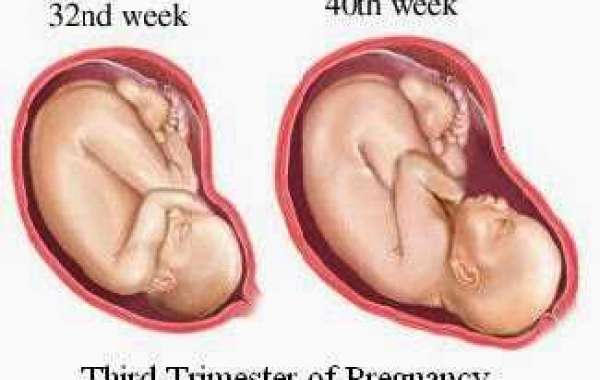

Фотографии и советы по третьему триместру беременности